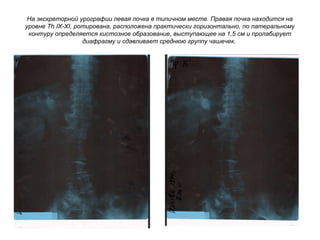

На экскреторной урографии левая почка в типичном месте. Правая почка находится на

уровне Th IX-XI, ротирована, расположена практически горизонтально, по латеральному

контуру определяется кистозное образование, выступающее на 1,5 см и пролабирует

диафрагму и сдавливает среднюю группу чашечек.

Экскреторная урография. Боковая проекция